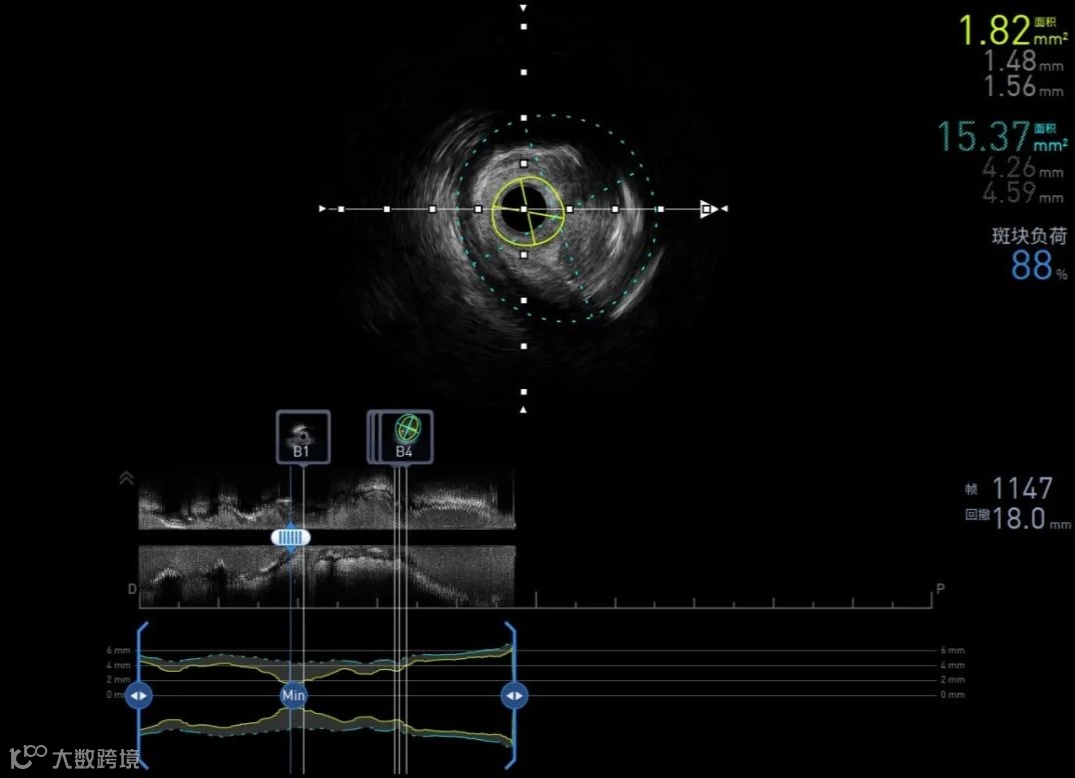

60MHz 术前LCX

pullback speed 0.5 mm/s

ALA展示血管辅助测量结果